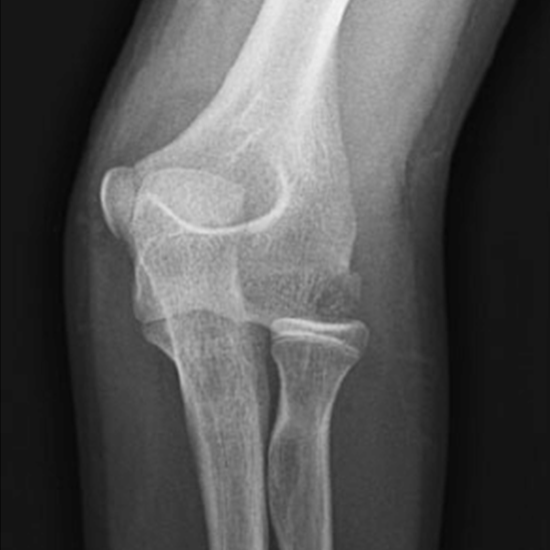

The elbow region consists of the forearm bones, upper arm, and elbow joint. In an anterior-posterior (AP) projection, the elbow joint is displayed in its standard anatomical location. The LAT projection is a view of the AP elbow at a 90-degree angle. It identifies chronic elbow joint soreness.